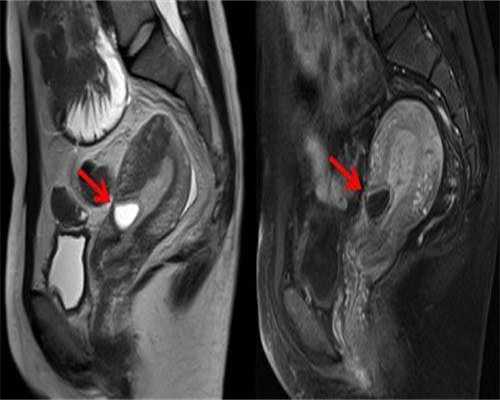

输卵管的正常功能是女性正常受孕的必要条件。输卵管发炎后,不仅会出现堵塞或粘连现象,还可能影响其他生殖器官的健康。多数女性在患上输卵管炎后会出现腹痛、腹胀等症状。